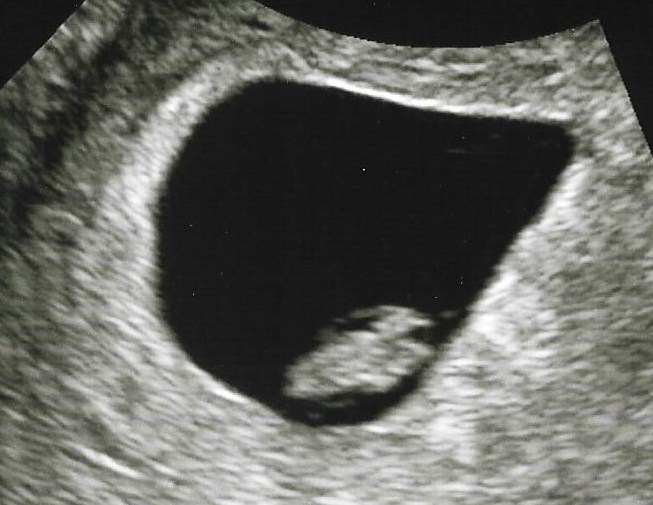

I had my first u/s today. I saw my little peanut with a heartbeat of 130!!!! He/She was also measuring 2 days ahead so my due date will still stay Sept 21st. I can finally believe that this is real now!!!